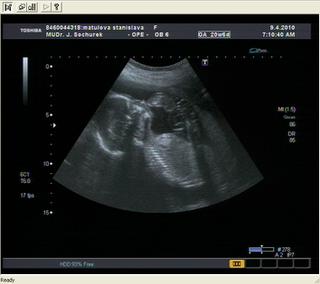

liptonek (26let, SP12/2009 Femibion)..............................................................................8.4.//